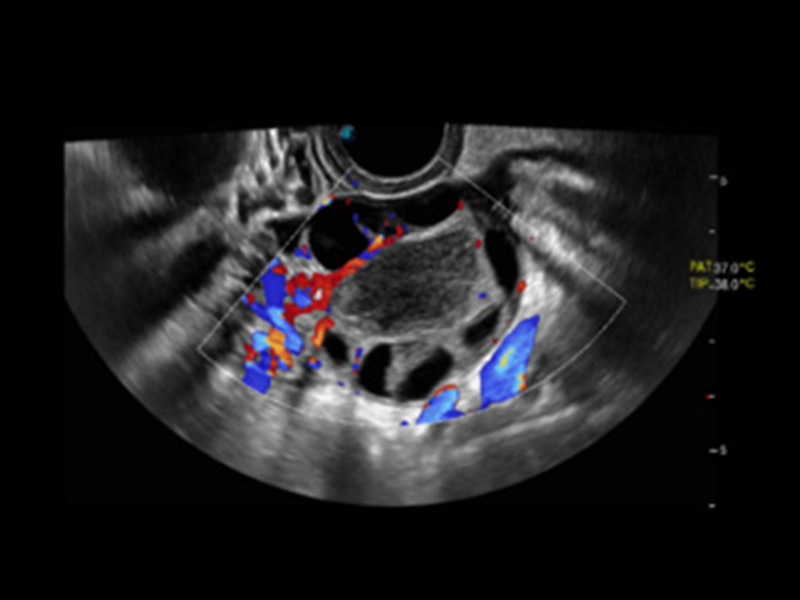

Micro F

Ermöglicht die Visualisierung von mikrovaskulären Strukturen

Micro F bietet eine innovative Methode, um den sichtbaren Fluss in der Ultraschallbildgebung zu erweitern, insbesondere um den langsamen Fluss kleiner Gefäße sichtbar zu machen. Durch die Verwendung eines fortschrittlichen adaptiven Filters und die Akkumulation von zeitlichen und räumlichen Signalen kann Micro F den geringen Blutfluss effektiv von der Bewegung umgebendem Gewebe unterscheiden und die Hämodynamik mit höherer Empfindlichkeit und räumlicher Auflösung darstellen.

• Zervikales schlecht differenziertes Karzinom mit Micro F

• Fetale Pericallosal-Arterie mit Micro F

• Fetale einseitige Kleinhirnhypoplasie mit Micro F

• Fetaler Leberblutfluss mit Micro F